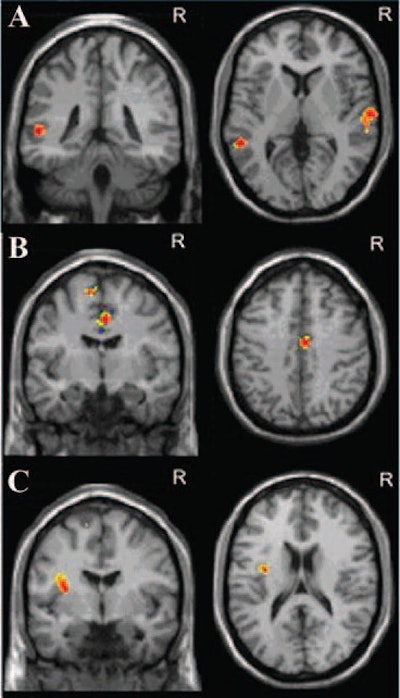

| Axial and coronal MR images show correlation between default mode network functional connectivity and severity of early anxiety symptoms. Anxiety symptom severity measured at 10-day follow-up correlates positively with functional connectivity index in (A) left and right middle temporal cortices and correlates negatively with (B) anterior midcingulate cortex and (C) left insula. Images courtesy of Radiology. |

The authors attempted to correlate depression severity on the HDRS 17 and HARS scales with functional activity in various brain areas at different follow-up times on fMRI.

With respect to early mood symptoms, the researchers found no correlation between HDRS 17 depression score and the functional connectivity index at the 10-day follow-up point. However, they found that the HARS score for anxiety correlated positively with the rest functional connectivity index of the right and left middle temporal cortex.

Regarding late mood symptoms at the three-month follow-up, the left middle temporal cortex rest functional connectivity index correlated positively with both the HDRS 17 and HARS scales.

"These results support a strong association between early resting-state network impairments and the risk of poststroke mood disorders," the authors wrote. "We found a strong association between [the middle temporal cortex] functional connectivity and mood symptom severity at early and late poststroke phases."